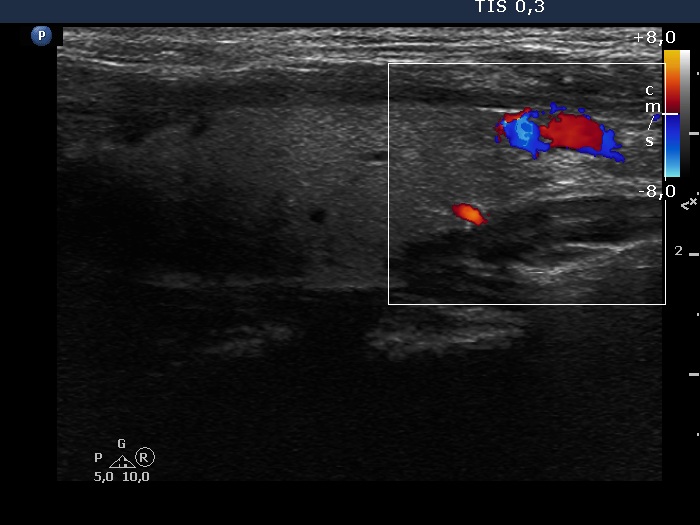

Halo sign and vascular pattern of nodules - case 971 (ultrasonographic picture 5)

Left lobe, longitudinal scan, color Doppler mode. It became evident that the deeply hypoechoic area is indeed a vessel.